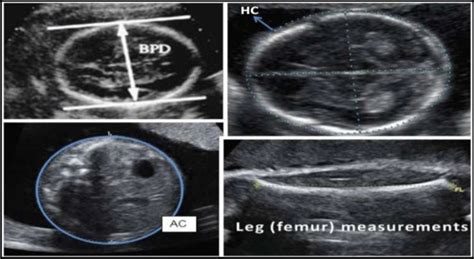

- BPD (Biparietal Diameter): This measures the diameter of your baby’s head from one side to the other. Think of it like measuring the widest part of their head. It’s one of the most common measurements and helps estimate how far along your pregnancy is and how well the head is developing.

- HC (Head Circumference): This measures the circumference, or the distance around, your baby’s head. It’s a key indicator of head size and brain development. Often, the HC measurement is used together with the BPD measurement for a more accurate assessment.

- AC (Abdominal Circumference): This measures the circumference of your baby’s abdomen. This measurement helps assess the baby’s weight and overall growth. It’s particularly useful in detecting potential issues like growth restriction or, on the other hand, the baby is too big for the gestational age.

- FL (Femur Length): This measures the length of your baby’s femur, which is the thigh bone. The FL can be used to estimate your baby’s gestational age and size, just like the other measurements. It’s an important measurement because it can provide clues about skeletal development.